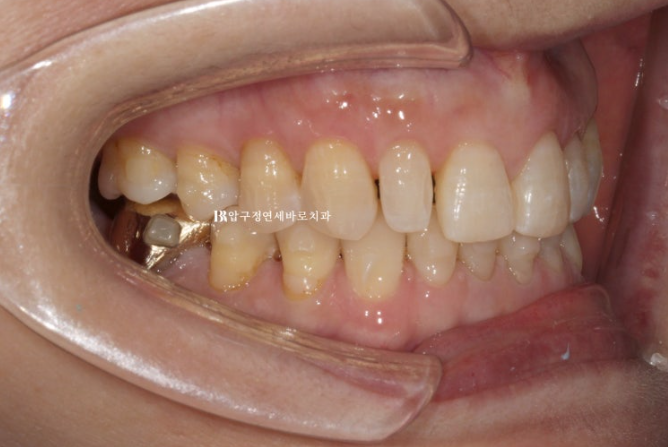

24.08

To match the patient’s desire for naturalness, the tooth shapes were designed to exclude artificial elements as much as possible.

Just as wrinkles increase on the face, our teeth also show their age quite clearly.

The gums gradually recede, and there are more craze lines in the teeth.

There is also more wear, chipping, and darkening in color.

This photo lets you check the thickness of Gelami.

Even though it is no-prep, the teeth do not feel thicker than before.